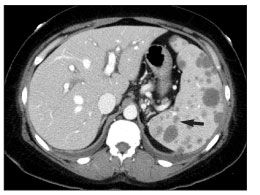

An abdominal CT scan showed an abnormally enlarged, heterogeneous spleen with innumerable, low-attenuation, hypodense lesions (Figure 1). Prominent porta hepatis lymph nodes were visualized; other lymph nodes were unremarkable. Evidence of hepatomegaly and gallbladder wall thickening was demonstrated. Discrete hepatic lesions were not seen.

Figure 1.CT scan of the abdomen showing enlargement of the spleen (16 cm in the anterior/posterior direction) with low-attenuation lesions (arrow) and hepatomegaly (20 cm in the craniocaudal direction) with no discrete lesions. (Image courtesy of the department of nuclear medicine, New York Presbyterian Hospital–Weill Cornell Medical College.)